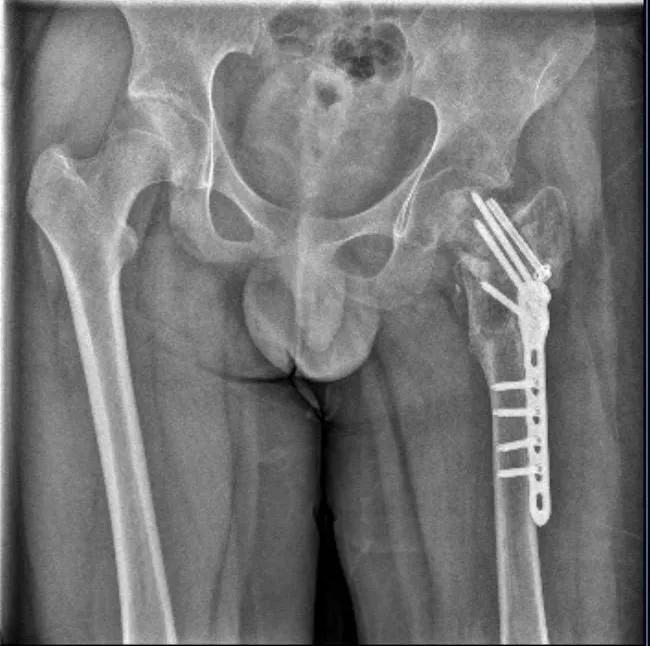

然而此后,四维基地仍继续招生运营。2024年,武女士听一名家长说,基地里的孩子更多了,有孩子“因为逃跑被吊着打”。武女士再次报警。7月,晋江市公安局对小武被故意伤害一案立案侦查。随后,晋江市公安局对小武进行了人体损伤程度鉴定,8月29日出具的《鉴定意见通知书》显示,小武三个部位不同程度损伤,其中,“左髋部重伤二级,胸部轻伤一级,双下肢轻微伤”,同时,其左股骨打了钢针、钢板。同年9月14日,向明胜因涉嫌过失致人重伤罪,被晋江市公安局刑拘,次日取保候审,10月19日,晋江警方再次将向明胜刑拘。10月中旬至下旬,何某坡、张某宇、洪某鑫三名老师也先后被刑拘。2025年9月,经晋江市检察院公诉,向明胜涉嫌故意伤害罪和虐待被监护、看护人罪两起罪名,何、张、洪三名教官涉嫌虐待被监护、看护人罪一案,在晋江市法院开庭审理。